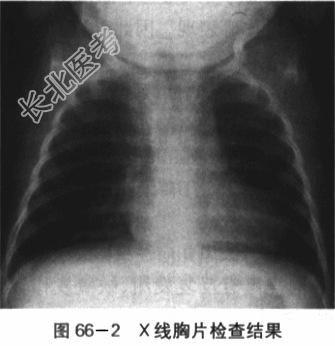

- [材料题] 患儿,男,2岁3个月,因"哭吵后口唇发绀伴气促1h"就诊。患儿入院前1h剧烈哭吵后出现口唇发绀、呼吸急促、家属安抚后无明显改善,送入急诊。出生6月龄前患儿无特殊病史,6月龄后患儿偶有哭吵后口唇青紫,增有剧烈哭吵后呼吸快,口唇发紫加重,安抚后好转;在当地住院发现有心脏杂音,做了一些检查后诊断心脏病(具体不详)。平素活动量少,喜静不喜动,喜抱,偶尔有走路时反复下蹲。目前饭虽少,身高、体重均不及同龄儿。大小便正常。患儿为G₁P₁,孕39周自然分娩。BW3200g。否认孕期感染或服药史,否认围产期窒息缺氧病史。否认家族心脏病或其他遗传病史。体格检查:T37℃,P148次/min,R52次/min,BP78mnlHg/40mmHg,Wt10.1kg,Ht78cm,SaO₂68%。烦躁,全身大汗,口唇发绀,可见杵状指,四肢脉搏稍弱,对称。肺部检查两肺呼吸音粗稍粗,未及明显啰音。心前区饱满,心尖搏动位于第4肋间左乳线上,范围约2cm;HR118次/min,规则,2~3LSB SMⅠ~Ⅱ级,粗糙,P2略增强,无分裂。腹部平软,肝脏肋下2.5cm,质地软。脾未触及。双下肢无水肿。实验室检查(1)心电图检查:窦性节律,右房、右室增大。电轴右偏,Ⅱ导联P波高尖,呈双峰,时限=0.12s。V₁导联QRS波群呈R形,V₅导联QRS波群呈RS形;ST段压低,V₃~V₅导联T波倒置。如图66-1所示。(2)X线胸片检查:右房、右室大。心胸比例0.65,心影呈"靴型"心,心尖圆钝、上翘;肺动脉端内凹,肺血少。如图66-2所示。(3)超声心动图检查:心脏位置及连接正常。右房、右室增大,右室壁肥厚,左室收缩活动正常。主动脉增宽,骑跨于室间隔上50%。左右冠状动脉开口可见,肺动脉瓣及瓣下狭窄,瓣环0.67cm,总干内径1.29cm,流速2.3m/s,右室流出道狭窄肌肉肥厚,过此处血流少,流速约2.8m/s。左肺动脉开口0.82cm,内径0.97cm;右肺动脉开口10.78cm,内径0.85cm。房室瓣开放活动可。房间隔完整。室间隔缺损,对位不良型,双向分流。左位主动脉弓。如图66-3所示。